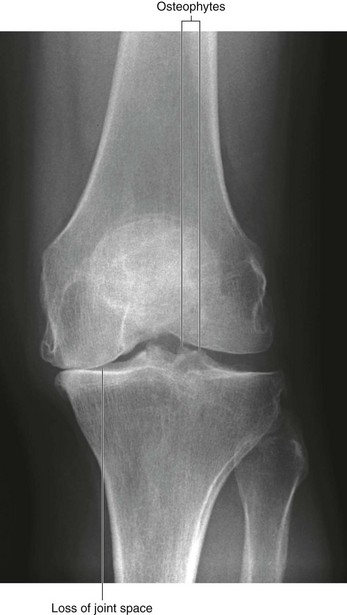

In the clinic Degenerative joint disease

Degenerative joint disease is commonly known as osteoarthritis or osteoarthrosis. The disorder is related to aging but not caused by aging. Typically there are decreases in water and proteoglycan content within the cartilage. The cartilage becomes more fragile and more susceptible to mechanical disruption. As the cartilage wears, the underlying bone becomes fissured and also thickens. Synovial fluid may be forced into small cracks that appear in the bone’s surface, which produces large cysts. Furthermore, reactive juxta-articular bony nodules are formed (osteophytes). As these processes occur, there is slight deformation, which alters the biomechanical forces through the joint. This in turn creates abnormal stresses, which further disrupt the joint (Figs. 1.23 and 1.24).

image

Fig. 1.23 This radiograph demonstrates the loss of joint space in the medial compartment and presence of small spiky osteophytic regions at the medial lateral aspect of the joint.

In the United States, osteoarthritis accounts for up to one-quarter of primary health care visits and is regarded as a significant problem.

The etiology of osteoarthritis is not clear; however, osteoarthritis can occur secondary to other joint diseases, such as rheumatoid arthritis and infection. Overuse of joints and abnormal strains, such as those experienced by people who play sports, often cause one to be more susceptible to chronic joint osteoarthritis.

Various treatments are available, including weight reduction, proper exercise, anti-inflammatory drug treatment, and joint replacement (Fig. 1.25).